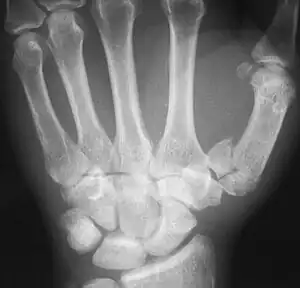

The Rolando fracture is a type of broken finger involving the base of the thumb.[1]

| Complete break at base of thumb | |

It is an intra-articular fracture.[2]

It was first described in 1910 by Silvio Rolando.[3] It is typically T- or Y-shaped.[4]